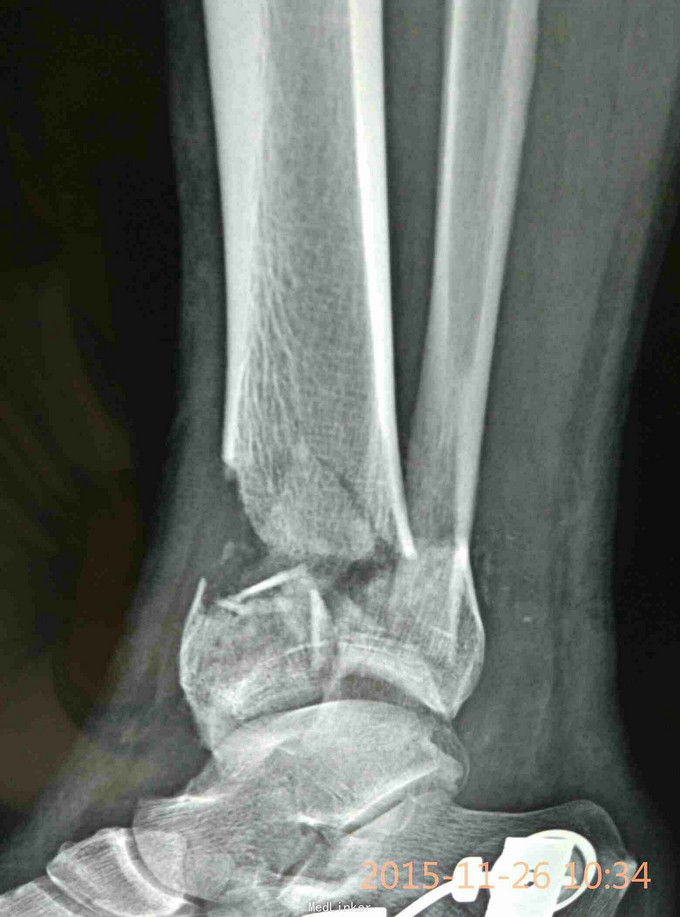

Pilon骨折,牵引10天

车祸致伤,开放性,急诊复位,跟骨牵引,清创,抗炎对症,伤口愈合可,无感染迹象,欲手术治疗,请各位老师给点建议。

伤时左踝畸形肿胀,外踝上方见长约5cm不规则裂伤,骨端外露,踝关节功能丧失,足背动脉搏动有力

左侧Pilon骨折于急诊清创骨折复位缝合并行跟骨牵引治疗。欲10天后,皮肤条件允许后,限期手术

选择何种术式,内固定物?